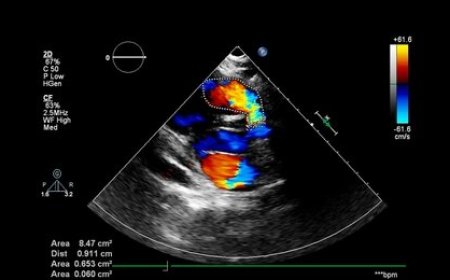

The Colour Doppler test is a non-invasive ultrasound used to assess blood flow i...